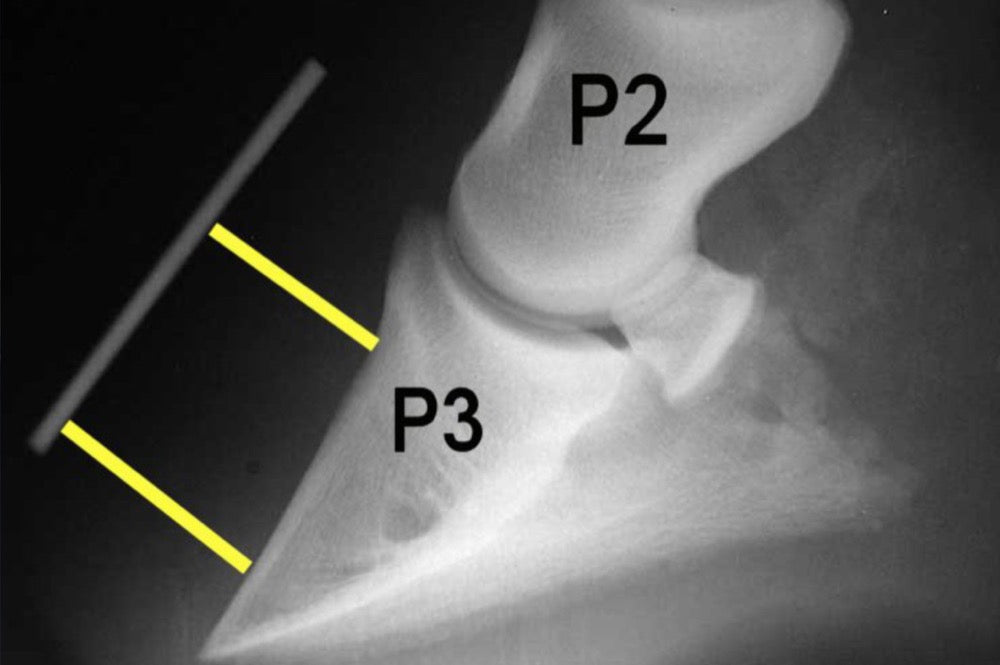

The laminae are responsible for supporting the pedal bone in the hoof and therefore the weight of the animal. In severe cases of laminitis the pedal bone can sink and rotate due to the inability of the damaged laminae to support it, and from the pull of the deep digital flexor tendon. If the pedal bone sinks too far, it can be seen to protrude from the sole of the foot.

Horses or ponies suffering from laminitis should not be made to stand in a stream or to have their hooves cold hosed, although it may initially make them more comfortable, prolonged cold to their hooves will aggravate the condition. Your vet may advise that x-rays need to be taken of the feet to show how much (if any) rotation has occurred. A farrier may also need to attend under vet supervision to correct the rotation and make sure the feet are in the best condition to facilitate recovery.